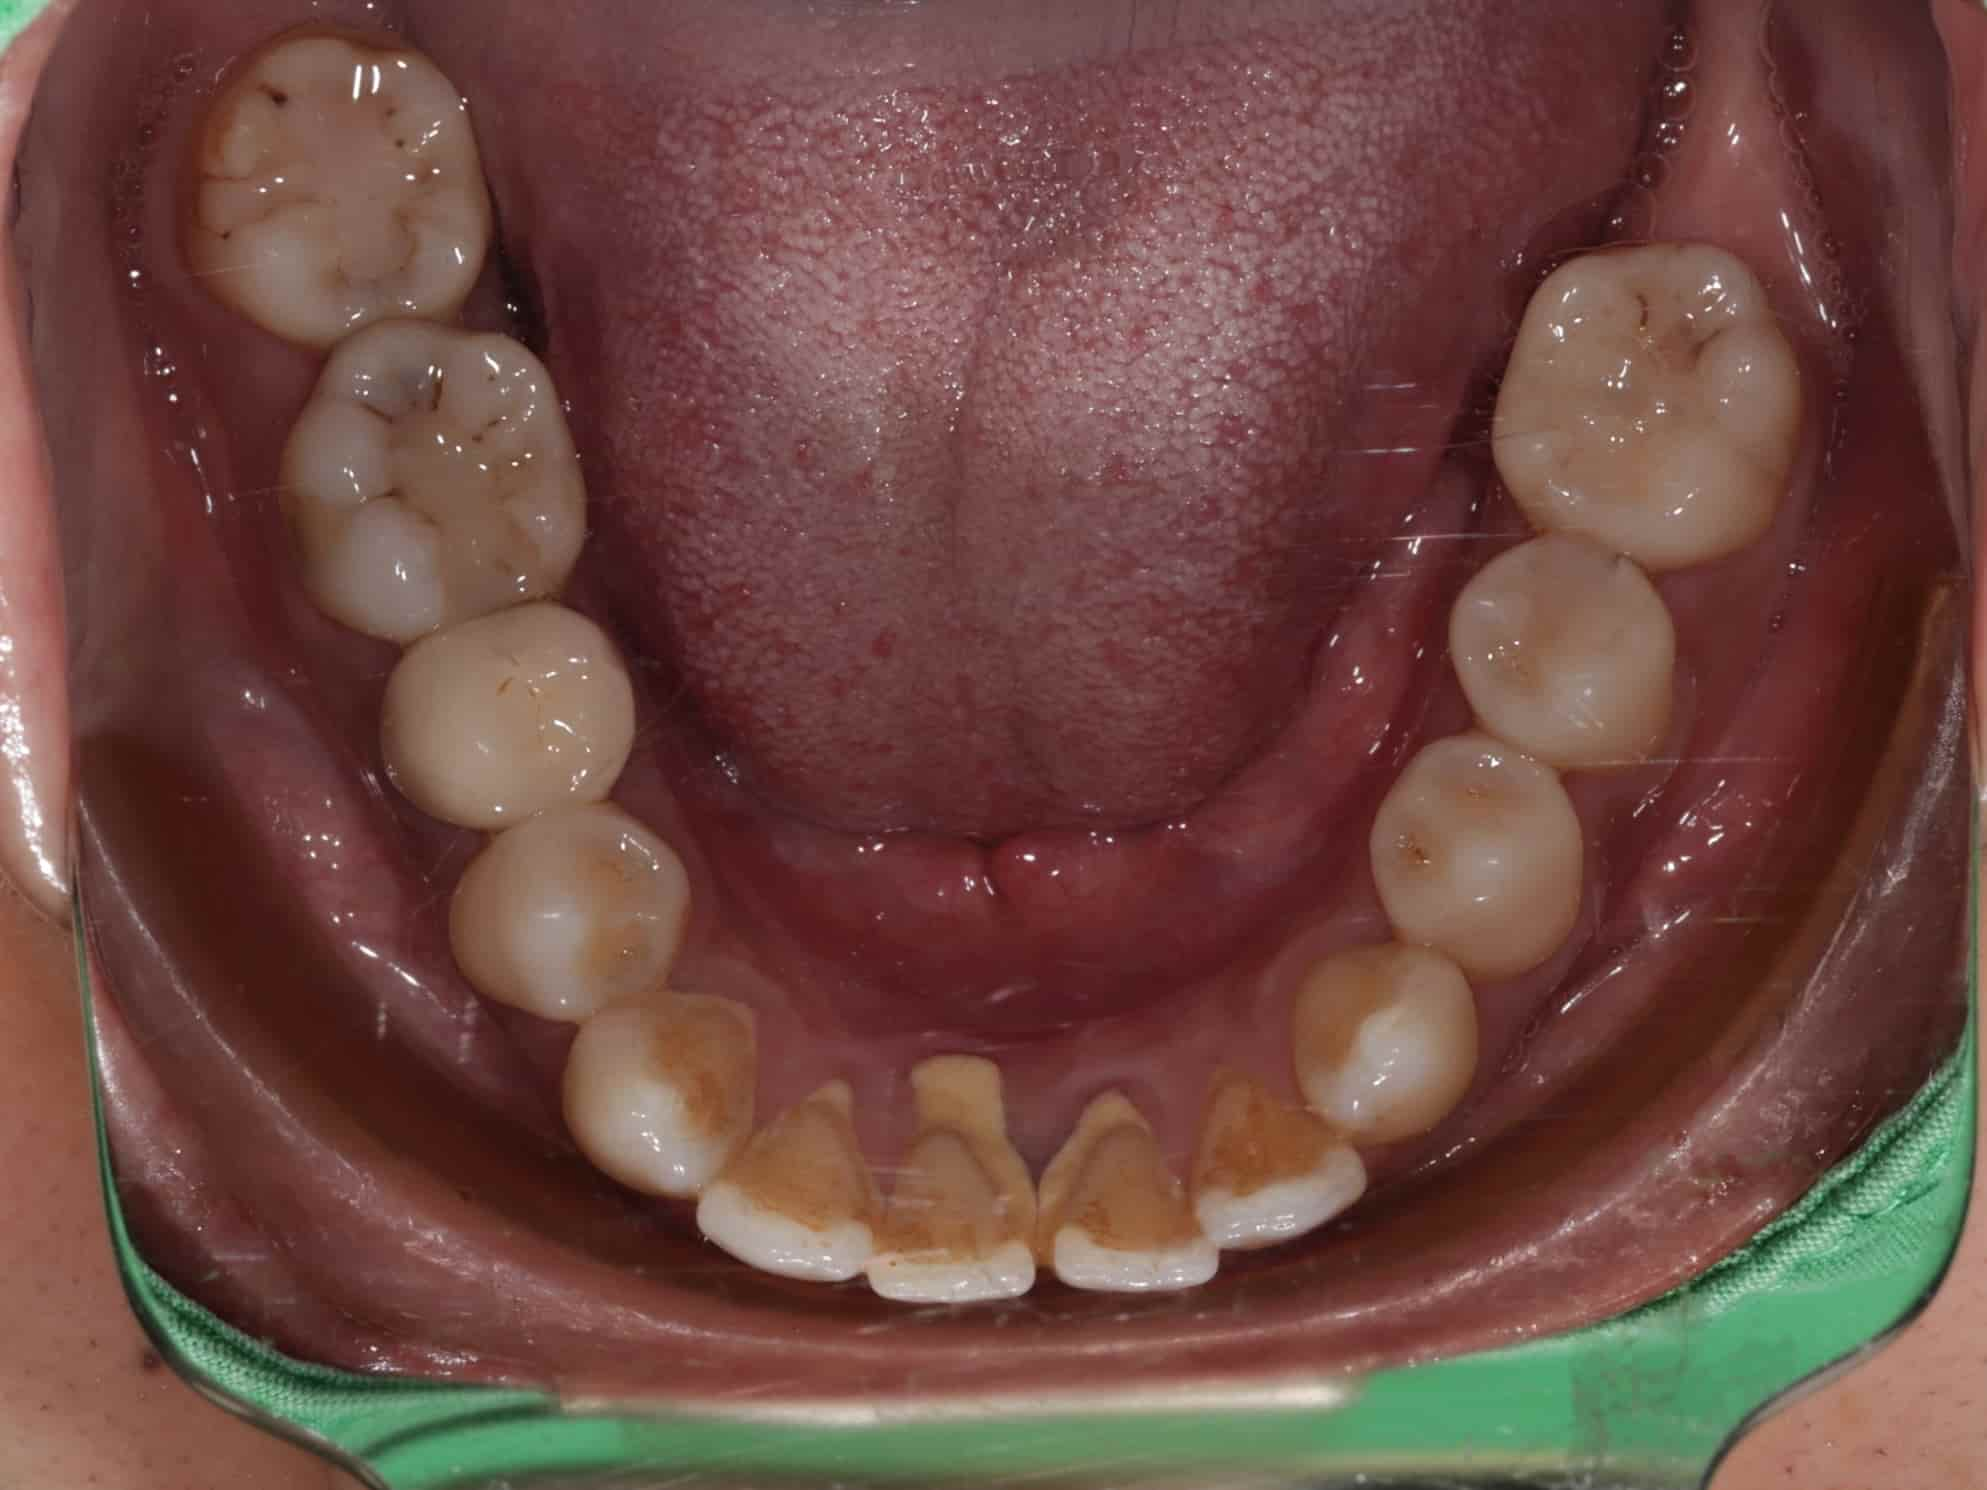

古小姐第一次來到診間時,主要是希望能做全口的詳細評估與檢查,因為她進食較黏稠的食物,牙齒容易感到疼痛,刷牙的時候容易出血,更令她困擾的問題是,她以前因為蛀牙拔掉牙齒,但沒有進行後續處理,左下方有缺牙的情況,除了導致牙齒開始出現縫隙,長期習慣用右邊進食,也讓她兩邊咬合都不太舒服。

經過全口檢查與評估後,我們發現古小姐的口腔問題相當複雜,主要可以歸納為以下幾個項目:

全口牙周病問題 - 導致刷牙時流血的主因

左邊缺牙問題 - 長期缺牙導致排列與咬合問題

咬合與牙縫問題 - 影響整體美觀與功能